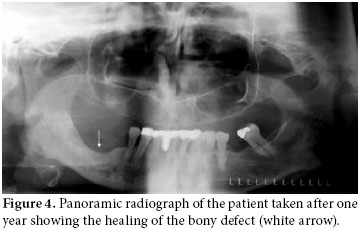

Together with the past history of long-term alendronate treatment and occurrence after tooth extraction, relevant clinical symptoms and conventional radiographic findings led to the suspicion of ONJ in this patient. We immediately ordered dental computed tomography (CT) which revealed sclerosis and osteolytic changes in the right mandible. This confirmed the diagnosis of osteonecrosis (Figures 2, 3). The patient also consulted with dental surgeons, and since there was no pathologic fracture, extra-oral fistulae, or osteolysis extending to the inferior border of the mandible, the disease was accepted to be in the second stage. Surgery was not recommended, and conservative management was started. The patient was advised to discontinue the alendronate treatment, and the etanercept treatment was also stopped. A good oral hygiene regimen using antibacterial tooth rinse was recommended. Her complaints and symptoms alleviated gradually. A control panoramic radiography taken after one year of bisphosphonate withdrawal displayed healing of the exposed bone (Figure 4).